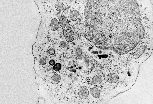

透射电镜(MET)下可见该巨噬细胞正通过两处细胞膜突起捕获 红细胞 。胞质内富含溶酶体(形态多样、有膜包绕、内容物致密的细胞器),表明该细胞参与细胞内消化过程。 |